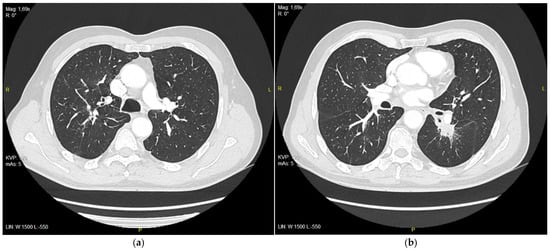

The patient continued on the treatment with good clinical effects. A partial response was observed on CT studies performed after 3, 6, and 9 months (Figure 3 and Table 1).

Figure 3. (a) Right upper lobe nodule after 9 months of treatment with erlotinib, 9 mm in diameter; (b) tumor in 6th segment of left lung after 9 months of treatment with erlotinib, 21 mm in diameter.